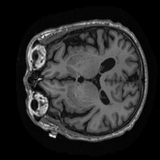

Sample MRI Scans

9 samples

Animated sagittal slices from ADNI-1 subjects across diagnostic groups

CN

CN Subject 3

Animated GIFs show 20 sagittal slices near the brain midline.